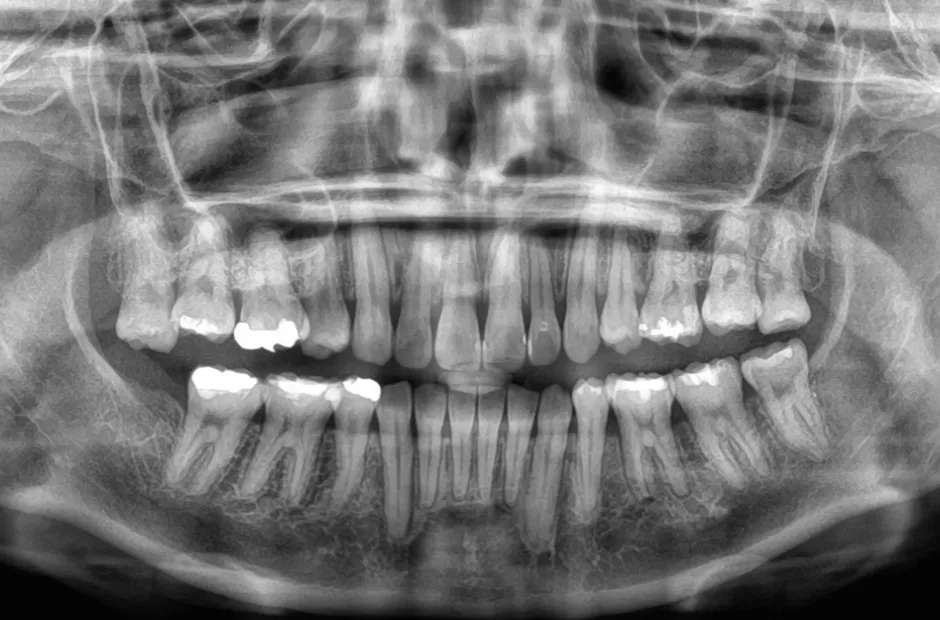

| 診断名・主訴 | 下顎前突、叢生 |

|---|---|

| 年齢・性別 | 23歳・女性 |

| 治療期間・回数 | 3年 |

| 治療に用いた主な装置 | 上顎5,5 下顎4,4 |

| 抜歯部位 | 舌側矯正 |

| 治療費 | 100万円(税抜) |

| リスク・副作用 | 装置による違和感・疼痛・歯肉退縮・歯根吸収・虫歯のリスクなど |

治療前

治療後